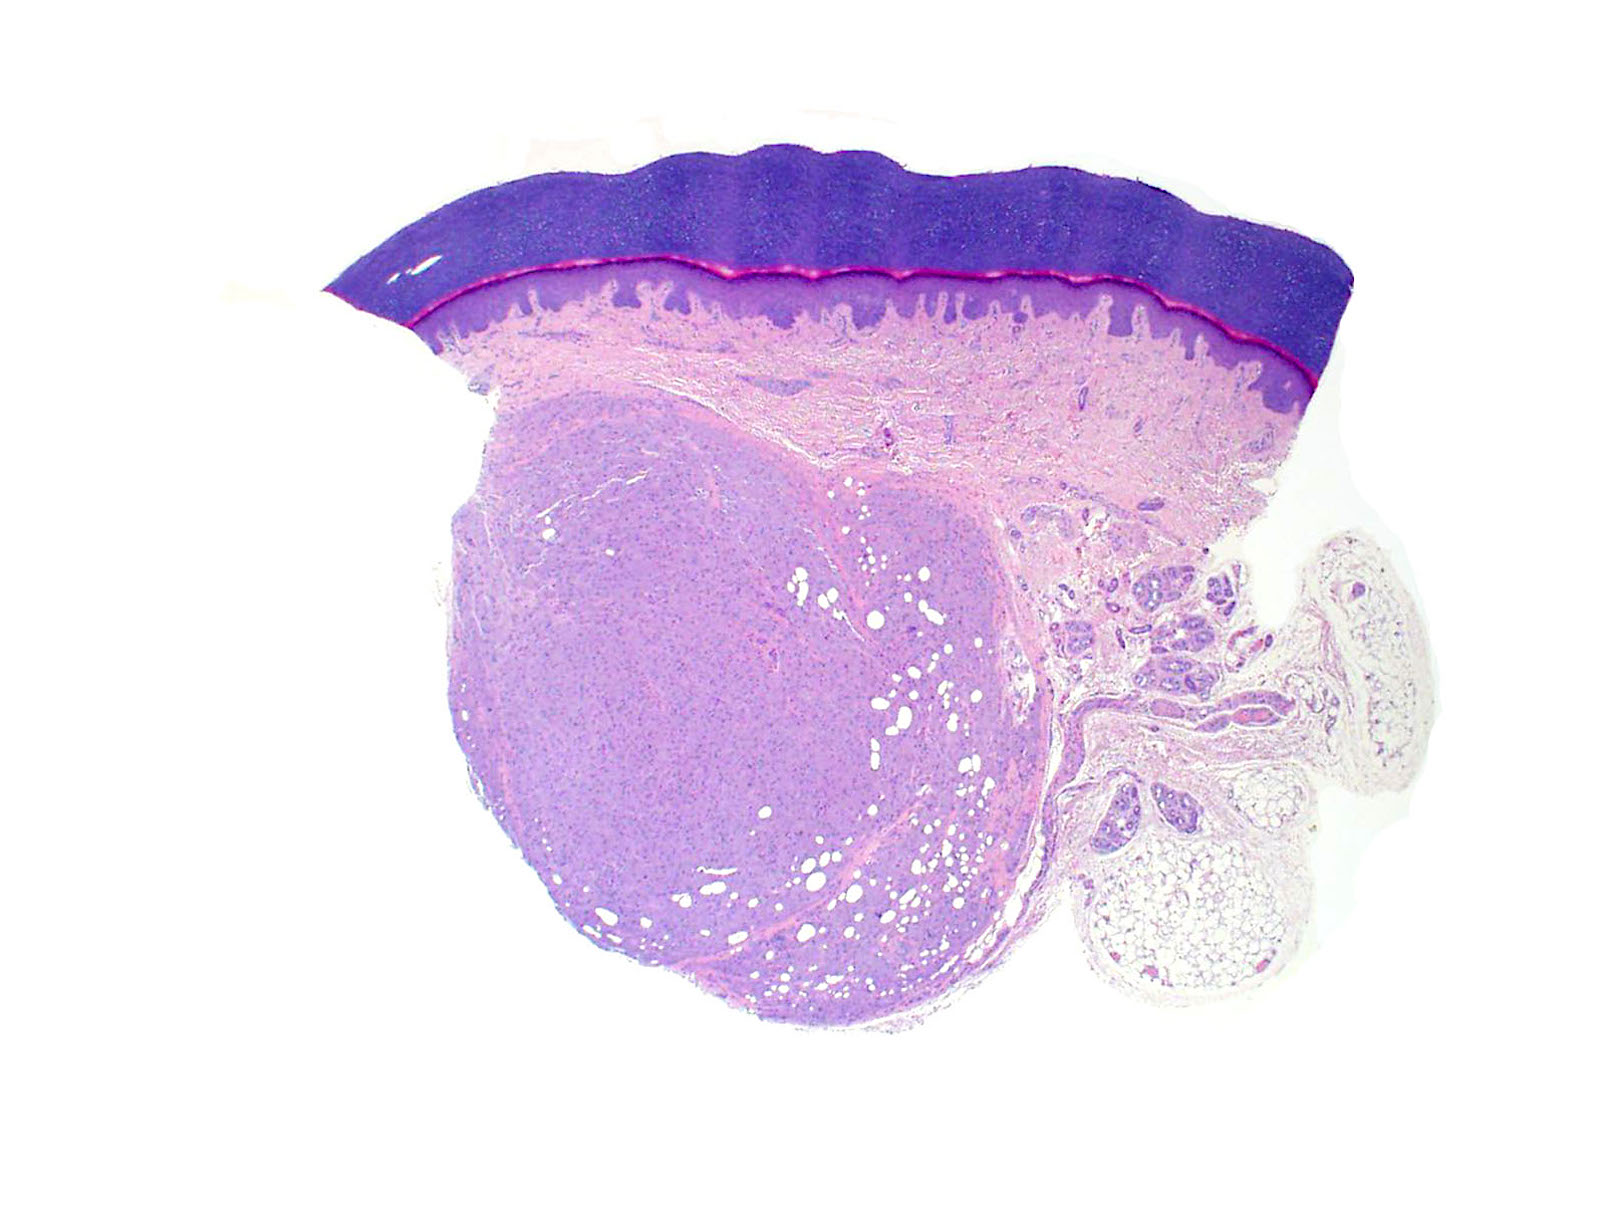

Microscopic (histologic) description

- Infiltrative or circumscribed architecture

- Can involve the subcutis

- Epidermis can show pseudocarcinomatous hyperplasia

Microscopic (histologic) images

Contributed by Jarish Cohen, M.D., Ph.D.